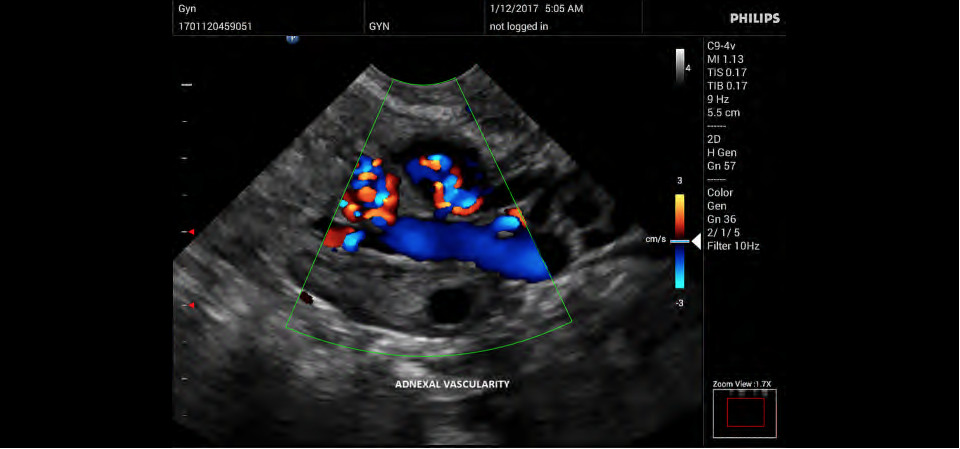

Philips InnoSight

Philips InnoSight увеличивает возможности сканирования во множестве мест оказания медицинских услуг. Благодаря данному УЗИ аппарату врачи могут не сомневаться в быстром выполнении обычных ультразвуковых сканирований во врачебном кабинете, клинике или больнице.

• Акушерство и гинекология;

• Цветное допплеровское картирование

• Специализация (УЗИ) - Общие исследования, Гинекология и акушерство

• Конвексный УЗИ датчик Philips C9-4v